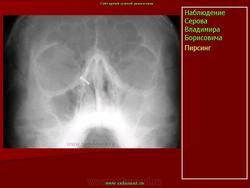

Инородные тела